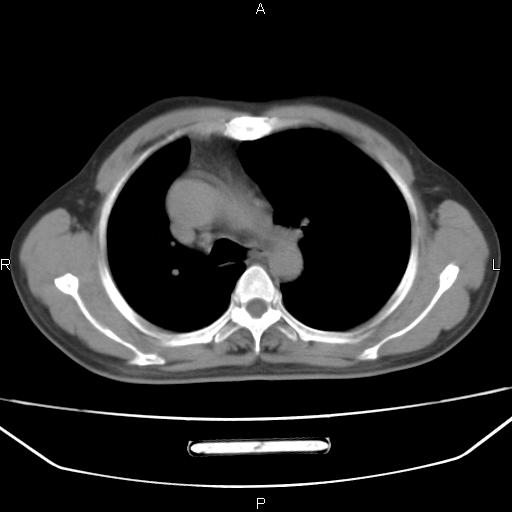

患者,男。50岁。近几日有咳嗽症状,无其他不适,既往病史无,考虑膈疝。请前辈们看看指导指导。

膈膨升,左下肺通气不良,膈肌好像还完整。

考虑左侧膈疝。

左侧膈疝。

符合隔膨升,膈肌较完整。